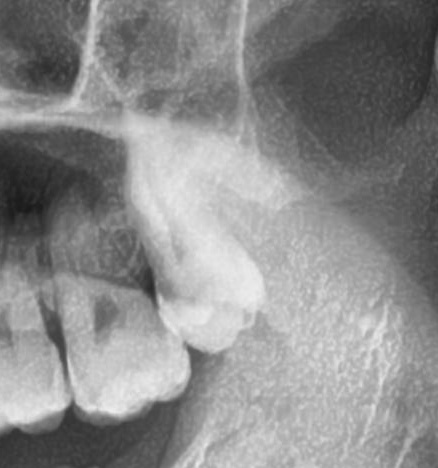

次にパノラマ写真を撮影してみると、左上の親知らずは歯ぐきの少し深いところで、手前の歯と並んでまっすぐに生えていることが確認できました。